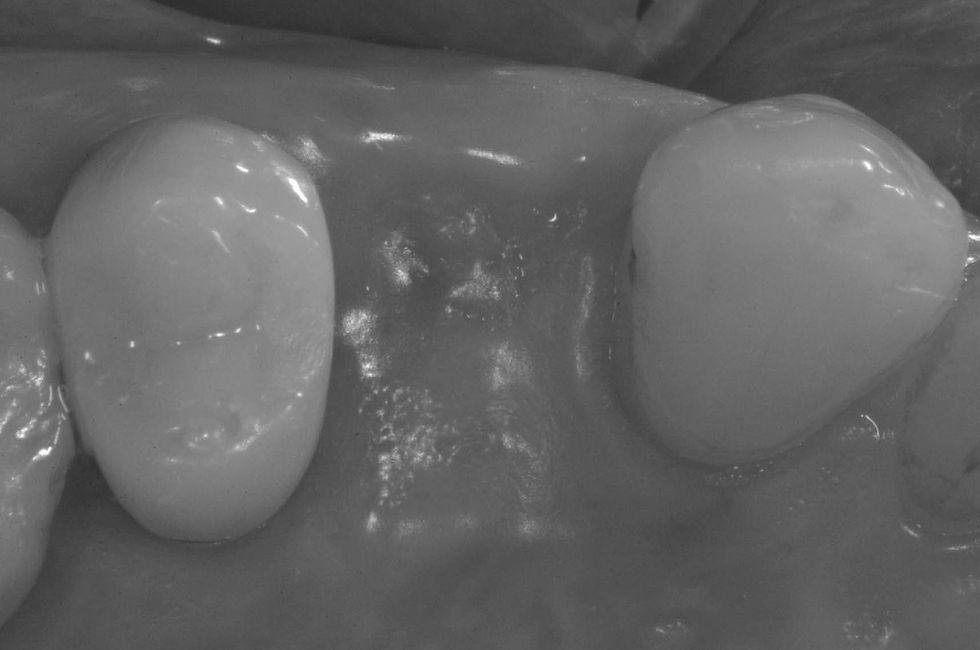

Occlusal view of the post-extraction socket with evidence of loss of the vestibular bone wall.